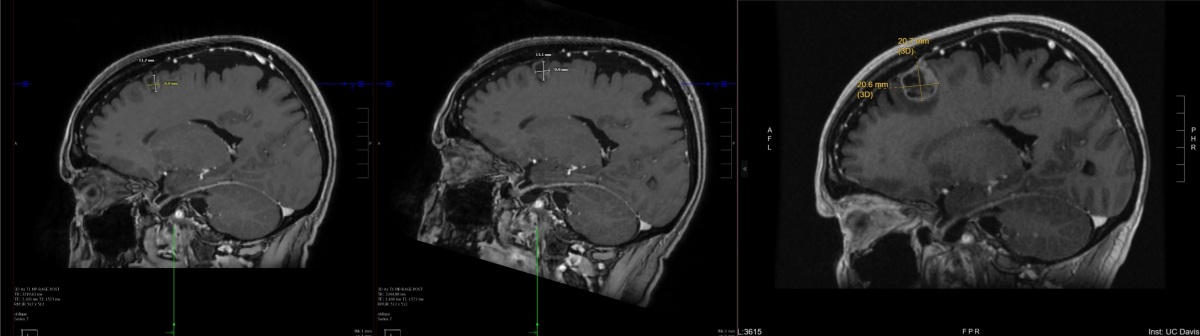

Progress brain scans - Left Lobe

From right to left, these images are of a spot of concern on my left frontal lobe that show the treatment effectiveness between the original scans in mid October, then the post treatment initiation scans from December and January. Initially, they wanted to drain and radiate these because of the size. My oncologist was pushing treatment first. I went with treatment first. And I'm glad I did because there's a strong possibility that I would be dead right now if I went the other way.